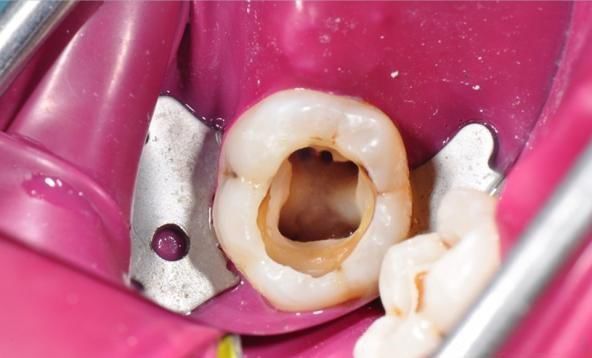

一、纱球咬半小时就该吐了

拔牙后,医生会在拔牙窝上方放置一个纱球让拔牙者咬紧,用以压迫止血。一般没有血液病的病人,在安静状态下咬紧纱球半小时就可以止血。